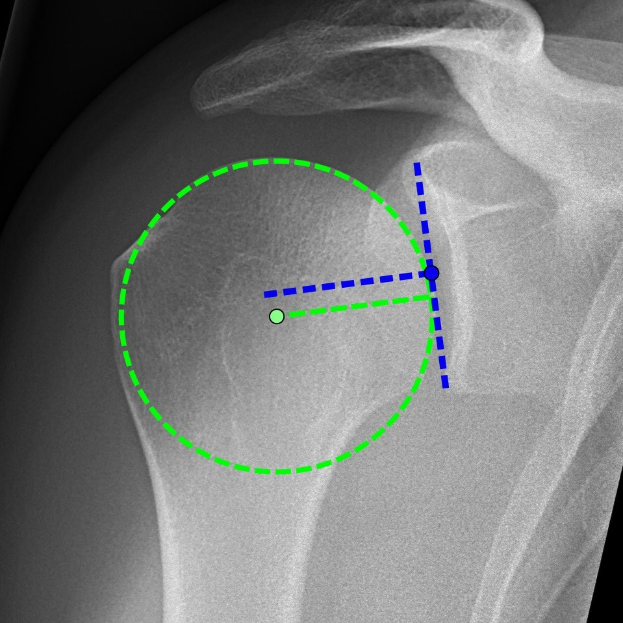

Ein Röntgenbild einer Schulter mit einem grünen Kreis, der die Lage eines Bandes markiert, umgeben von anderen Bändern.Nina Lehmann

Im Rahmen der zweiten Operation wurde die Implantation einer inversen Schulterprothese demonstriert. Während beider Eingriffe beantwortete Prof. Dr. Christoph Katthagen von der Universitätsklinik Münster Fragen der Zuhörerschaft in Echtzeit.